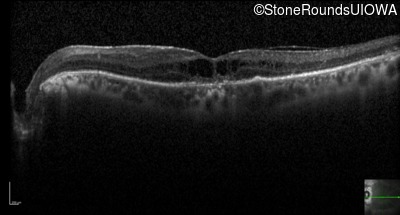

Optical Coherence Tomography - Right - 20/50 -1

Exemplar / OCT Stack

OCT Stack